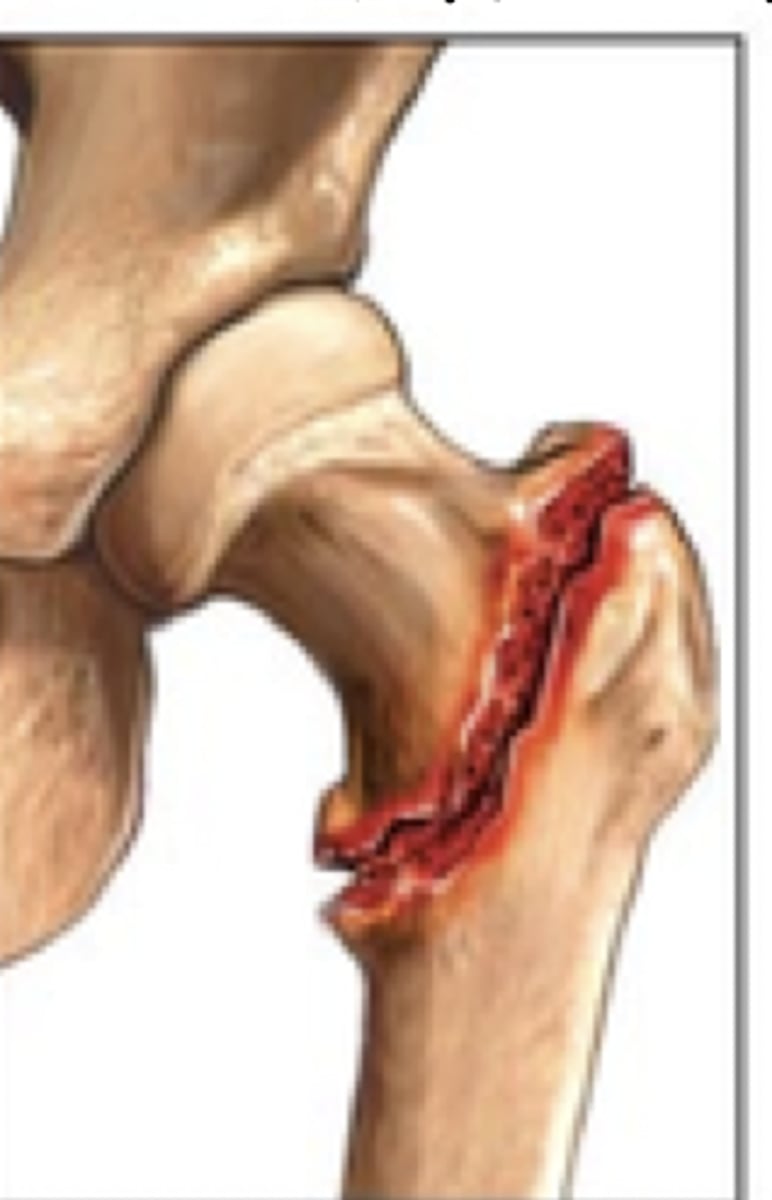

intertrochanteric fx

intertrochanteric fx

Comminuted intertrochanteric fracture. There is a fracture from the greater to the lesser trochanter (blue arrow). There are separate fragments of the greater trochanter (white arrow) and lesser trochanter (red arrow). There is varus deformity (white line) of the femoral shaft.